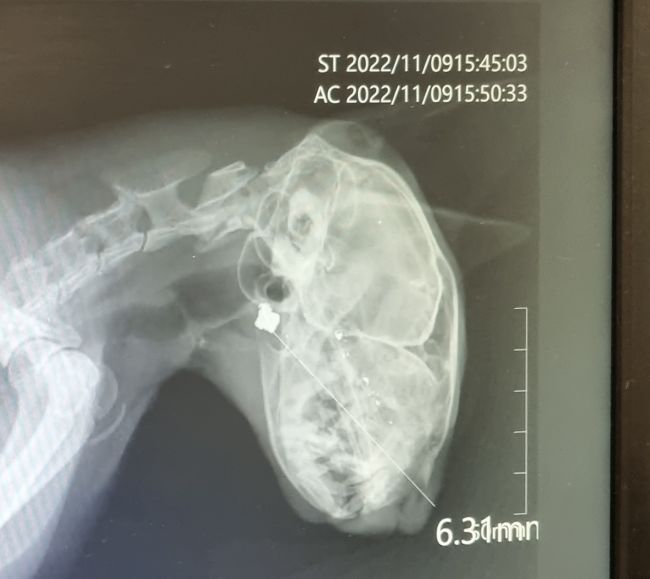

그리고 최근 한 살짜리 고양이는

얼굴 전체에 피를 흘리며 집으로

돌아왔습니다.

고양이의 주인은 즉시 병원에 데려갔고

코 안쪽에 총알이 박혀 있다는 것을

확인했습니다.